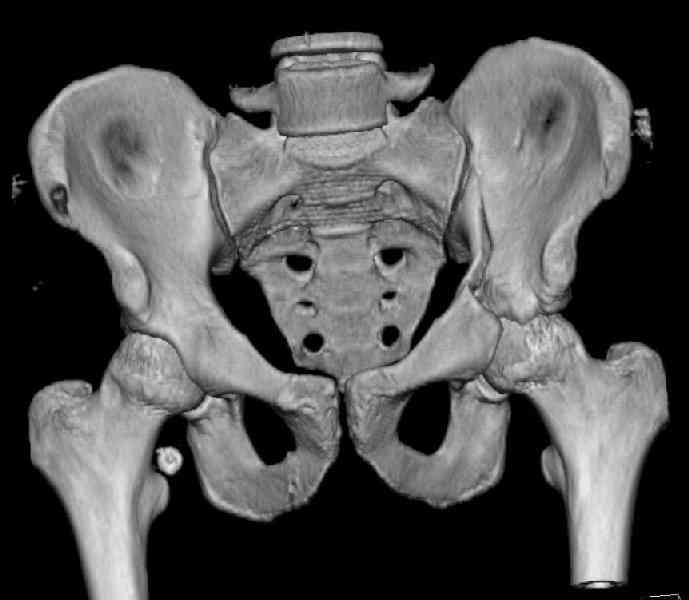

The last two images from the 3-D CT scan certainly makes the fracture look worse than the plan radiographs.

The joint is non-concentric as the head appears to be either "following the caudal segment", or the dome component is displaced from the tethered head... or so it seems... and he's young... so, many fracture surgeons would recommend reduction and fixation.

Some more images. Does it help to guess which part of the acetabulum is displaced?

Normal appearing SI joints and a healed posterior column limb... my bet's on caudal segment displacement.

The anterior element of the fracture is so low and the anterior roof arc angle must be at least 60 deg.

The posterior element is so minmally undisplaced. There is good congruence of the joint, and to top it all, 6 weeks have passed. If you consider ORIF now, I don't expect that much improvement could be accomplished. Not to mention the need for extensive approaches with their morbidity.